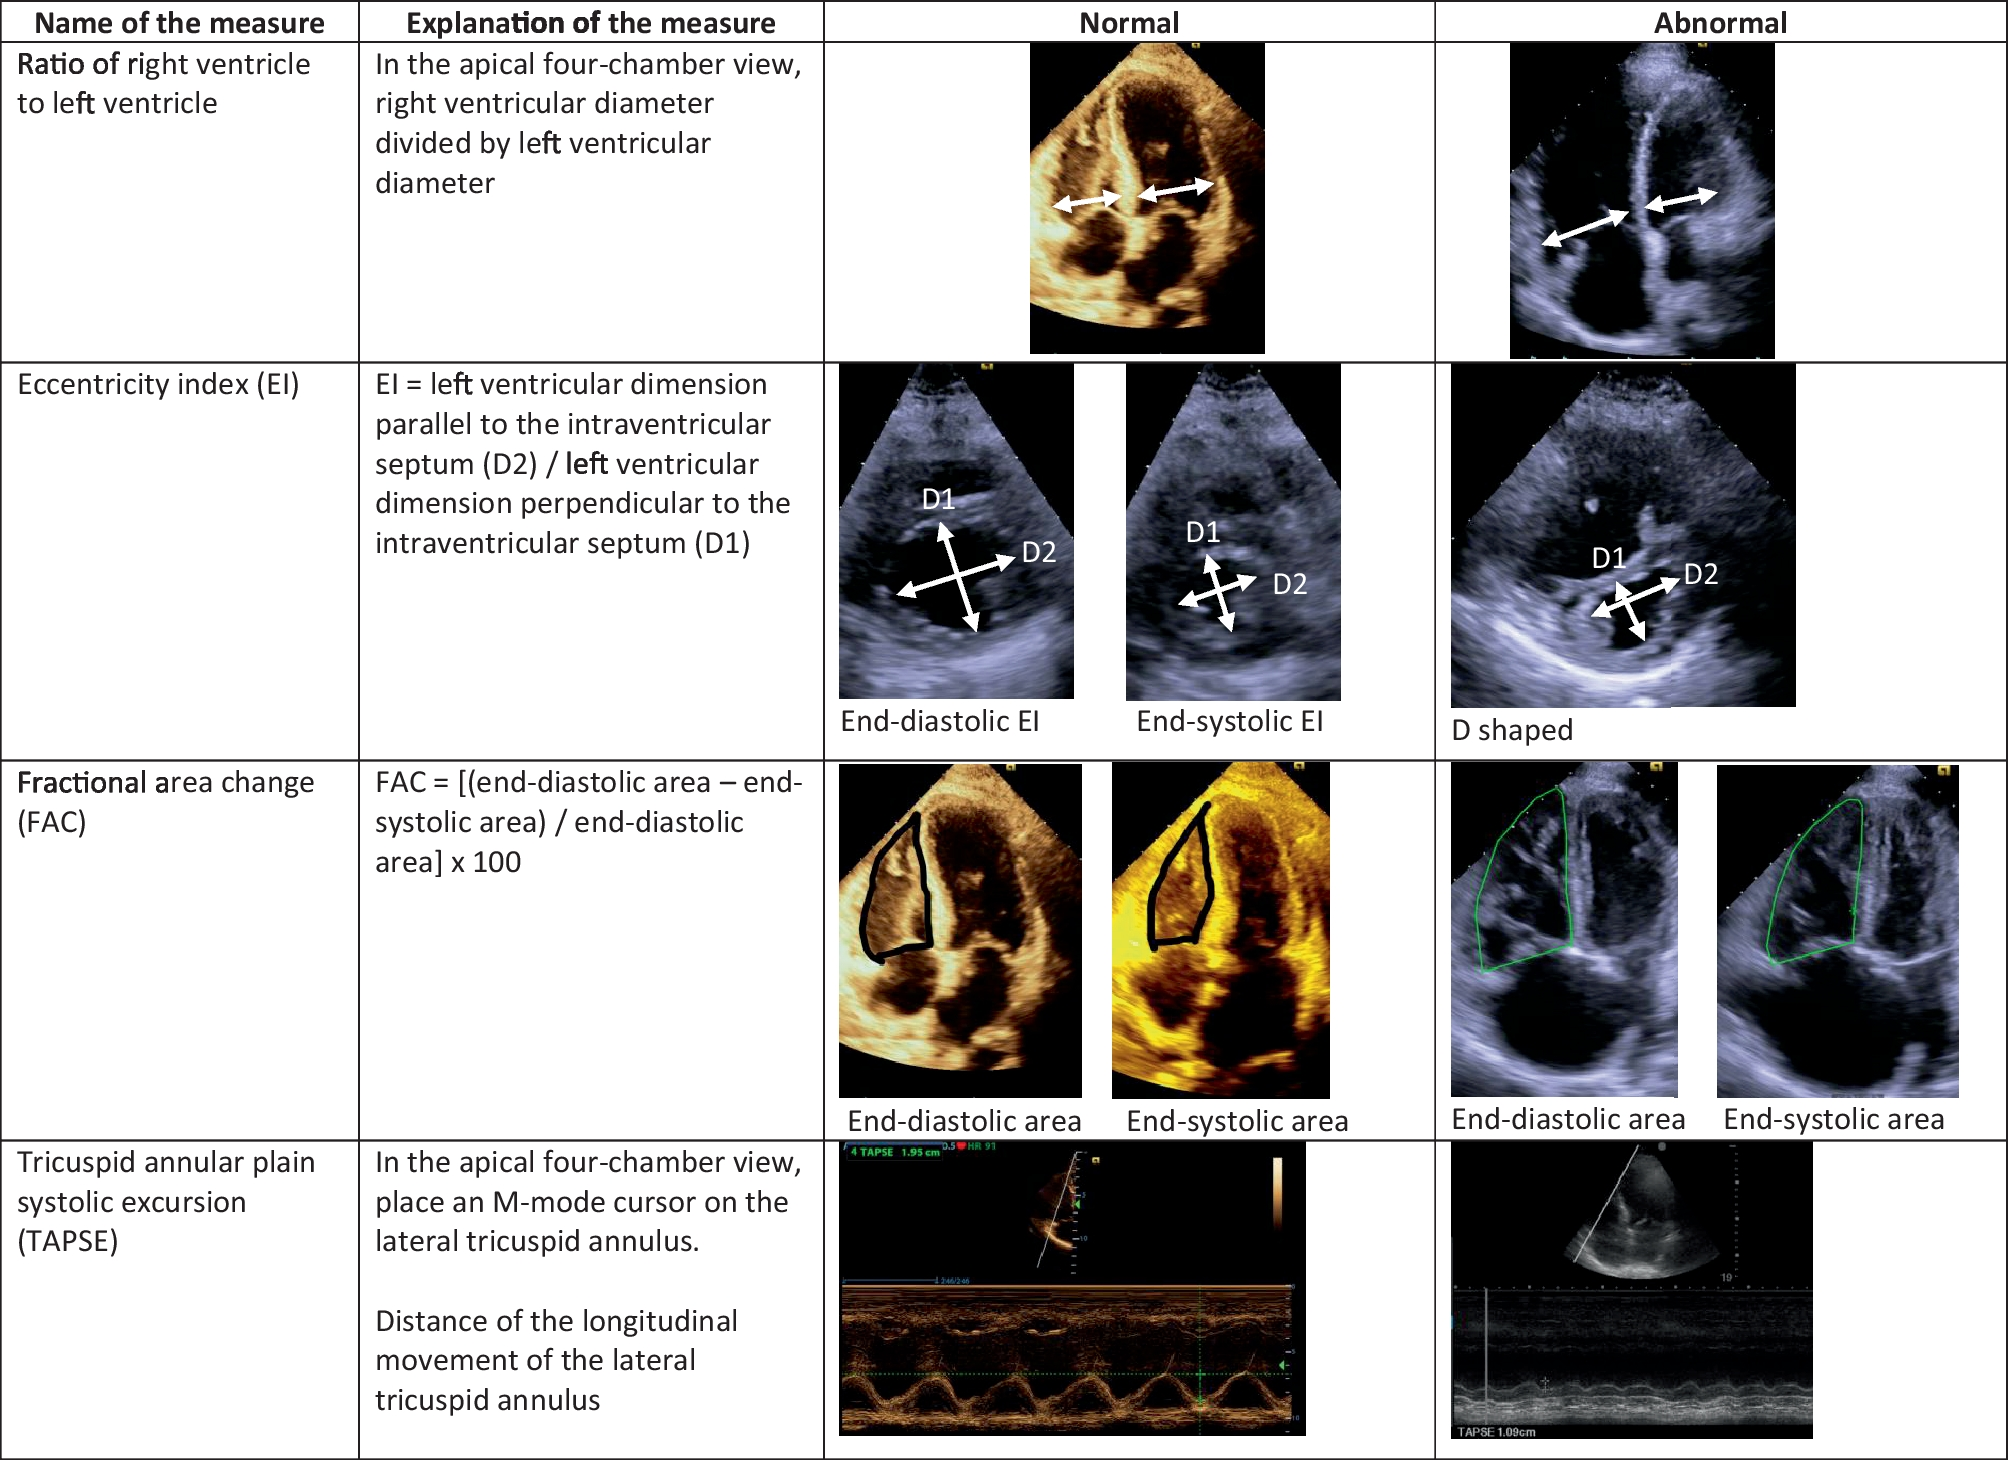

Challenges in Grading the Severity of Right Ventricular Dysfunction via Point-of-Care Echocardiography

This review discusses the current limitations of assessing the right ventricle (RV) using Point-of-Care Ultrasound, explai...

Current Pulmonology Reports